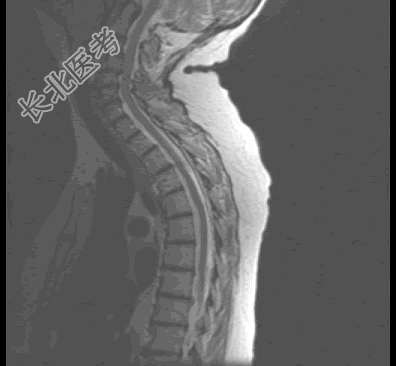

- 单项选择题患者,女, 68岁,头部剧痛伴左上肢无力半月余, 近两天发展为双下肢截瘫,请结合影像学检查, 选出最可能的诊断 ( )